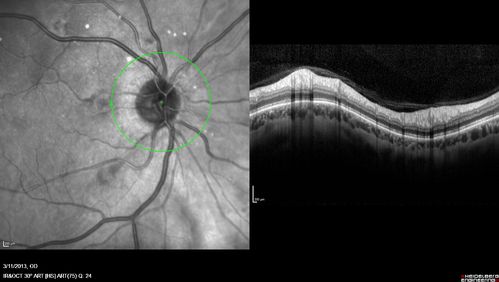

Malignant Hypertension - Cotton Wool Spots - Elschnig Spots - Optic Nerve Edema

Hypertensive Retinopathy - Cotton Wool Spots and Elschnig Spots and Optic Disc Edema - Malignant Hypertension